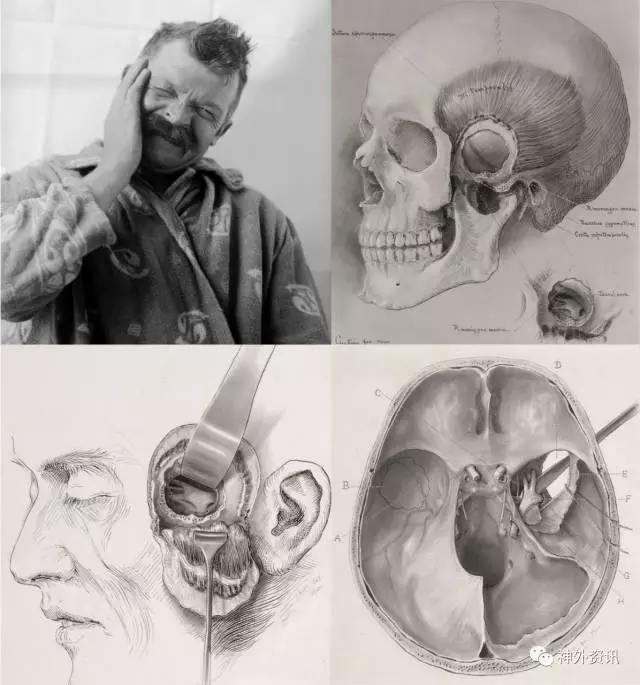

图1.Harvey Cushing 的首批三叉神经痛患者之一。这可能是最早描绘患者与该疾病的图片(上图)。Cushing原始素描图展示了颞下感觉神经剥脱手术(中、下图)(由耶鲁大学的Cushing中心提供)。